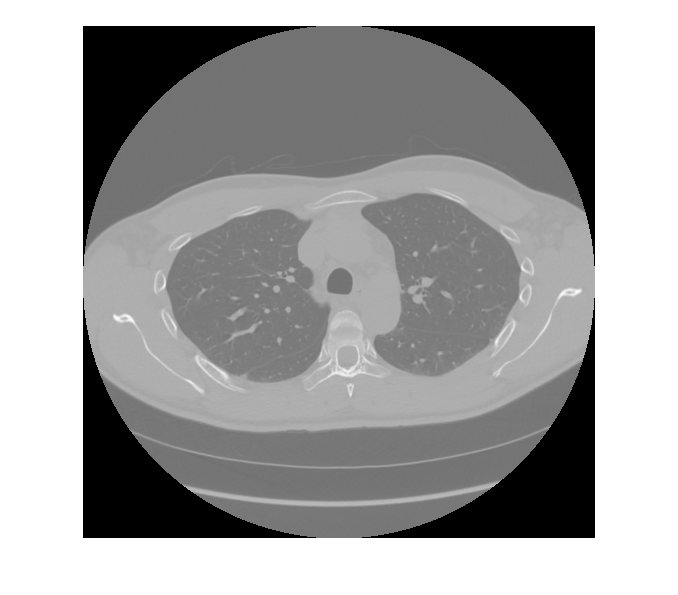

Visualize the raw pixel data.

figure

imshow(rawPixelData,[])

Visualize the rescaled pixel data.

imshow(rescaledPixelData,[])

Observe that rescaling changes the range of the pixel data.

[min(rawPixelData,[],"all") max(rawPixelData,[],"all")]

ans = 1×2 int16 row vector

-2000    2520

[min(rescaledPixelData,[],"all") max(rescaledPixelData,[],"all")]

-3024    1496